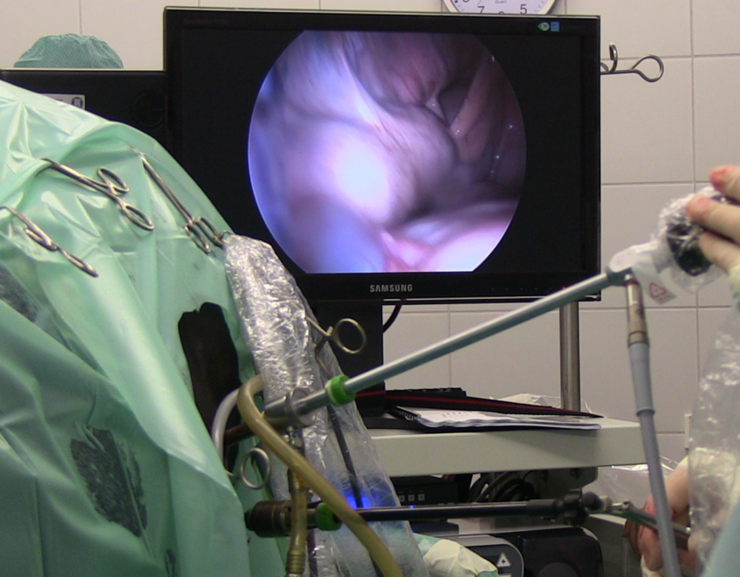

Arthroskopie - Gelenkoperation

- Minimalinvasive Eingriffe, wie die Arthroskopie (Gelenkspiegelung, z.B. zur Entfernung von Knochen-Knorpel-Chips“), und die Bursoskopie (Schleimbeutelspiegelung, z.B. des Hufrollenschleimbeutels) dienen der Diagnostik und Therapie von vielen verschiedenen Krankheitsbildern und werden in unserer Klinikregelmäßig und nach höchstem wissenschaftlichen Standard durchgeführt.

Tendovaginoskopie - Sehnenscheidenspiegelung

- Wenn eine vermehrte Füllung der Sehnenscheide („Galle“), z.B. im Bereich des Fesselkopfes, zur Entstehung einer Lahmheit beiträgt, führen wir eine sorgfältige Untersuchung mittels Ultraschall und Kontrastradiographie durch. Häufig ergeben sich dann bereits Hinweise auf einen Sehnenschaden innerhalb der Sehnenscheide.

- Im Rahmen einer minimalinvasiven Sehnenscheidenspiegelung (Tendovaginoskopie) wird der Schaden dann unter Sichtkontrolle geglättet und aufgefaserte Sehnenanteile werden entfernt, damit die Sehnenscheidenentzündung abklingen kann.

Laparoskopie – Bauchhöhlenspiegelung (z.B. Eierstockstumor und Kryptorchide)

- Die Laparoskopie oder Bauchhöhlenspiegelung ist eine minimalinvasive Operation. Durch einen kleinen Zugang („Schlüsselloch-Operation“) wird mit einer Kamera in die Bauchhöhle geschaut.

- Mit dieser Operationstechnik können am stehenden Pferd unterschiedliche Erkrankungen im Bereich des Geschlechtsapparates sowie des Darmtraktes untersucht und behandelt werden.